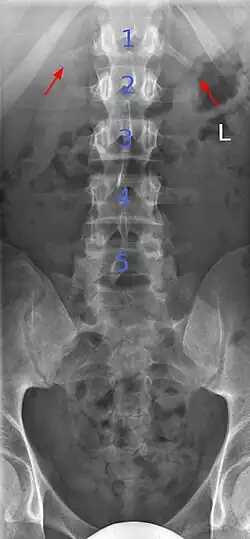

Lumbarization and sacralization

Lumbarization is an anomaly in the spine. It is defined by the nonfusion of the first and second segments of the sacrum. The lumbar spine subsequently appears to have six vertebrae or segments, not five. This sixth lumbar vertebra is known as a transitional vertebra. Conversely the sacrum appears to have only four segments instead of its designated five segments. Lumbosacral transitional vertebrae consist of the process of the last lumbar vertebra fusing with the first sacral segment. [1] While only around 10 percent of adults have a spinal abnormality due to genetics, a sixth lumbar vertebra is one of the more common abnormalities. [2]

Sacralization of the fifth lumbar vertebra (or sacralization) is a congenital anomaly, in which the transverse process of the last lumbar vertebra (L5) fuses to the sacrum on one side or both, or to ilium, or both. These anomalies are observed in about 3.5 percent of people, and it is usually bilateral but can be unilateral or incomplete (ipsilateral or contralateral rudimentary facets) as well. Although sacralization may be a cause of low back pain, it is asymptomatic in many cases (especially bilateral type). Low back pain in these cases most likely occurs due to biomechanics. In sacralization, the L5-S1 intervertebral disc may be thin and narrow. This abnormality is found by X-ray.

Transitional vertebrae

Transitional vertebrae have the characteristics of two types of vertebra. The condition usually involves the vertebral arch or transverse processes. It occurs at the cervicothoracic, thoracolumbar, or lumbosacral junction. For instance, the transverse process of the last cervical vertebra may resemble a rib. A transitional vertebra at the lumbosacral junction can cause arthritis, disk changes, or thecal sac compression. Back pain associated with lumbosacral transitional vertebrae (LSTV) is known as Bertolotti's syndrome. One study found that male German Shepherd Dogs with a lumbosacral transitional vertebra are at greater risk for cauda equina syndrome, which can cause rear limb weakness and incontinence.[11]